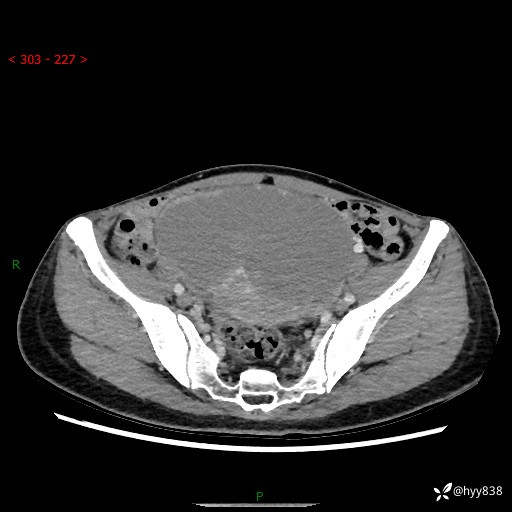

【患者信息】:女,50岁

【主诉】:外院超声发现腹盆肿块,为进一步诊治来我院,门诊已“盆腔肿块”收入院。

腹盆CT平扫+增强

【临床诊断】:盆腔肿瘤